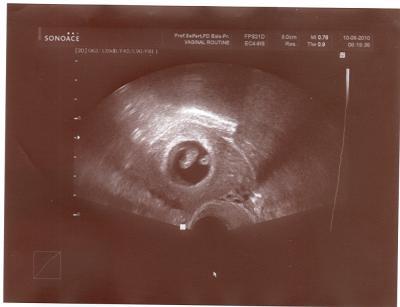

hier mal ein kleiner Gruß vom meinem Krümel in der 8. SSW. Ab morgen schreib ich schon die 9. Woche

Sag mal, sehe ich da evtl. 2 kleine Würmchen??

nein, das ist der Dottersack, den es schon abgeworfen hat!

Ich bekomme definitiv nur ein Baby!